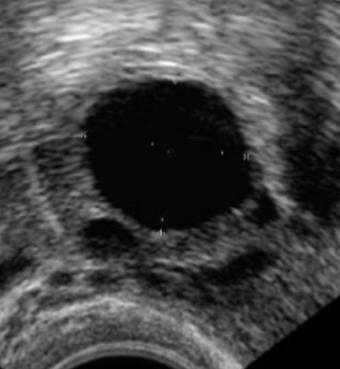

Figuur 2. Eierstok aan begin van de cyclus met kleine eiblaasjes en eierstok met dominant eiblaasje.

Afhankelijk van uw cycluslengte wordt enkele dagen vóór de verwachte eisprong een echoafspraak gepland in het IVF-centrum. Daarna is het afhankelijk van de groei van het ei-blaasje wanneer en of u nog een keer voor echocontrole moet komen. De controles zullen iedere één tot vier dagen plaats vinden tot het ei-blaasje groot genoeg is. Het streven is een ei-blaasje van 17 tot 18 mm. Bij deze grootte wordt de eisprong kunstmatig in gang gezet door de hCG-injectie (Ovitrelle®). De Ovitrelle® injectie zorgt ervoor dat de eisprong 38 tot 40 uur later plaatsvindt. De inseminatie wordt net voor deze periode gepland.

U krijgt een vervolgafspraak na vijf tot tien dagen (afhankelijk van uw cyclusduur of verloop van eerdere stimulaties). Na de tweede controle is het afhankelijk van de groei van het ei-blaasje wanneer en of u nog een keer voor echocontrole moet komen. De controles zullen iedere één tot vier dagen plaats vinden tot dat het ei-blaasje groot genoeg is. Het streven is (een tot) twee ei-blaasjes van 17 tot 18 mm. Bij deze grootte wordt de eisprong kunstmatig in gang gezet door de hCG-injectie (Ovitrelle®). De Ovitrelle® injectie zorgt ervoor dat de eisprong 38 tot 40 uur later plaatsvindt. De inseminatie wordt net voor deze periode gepland.